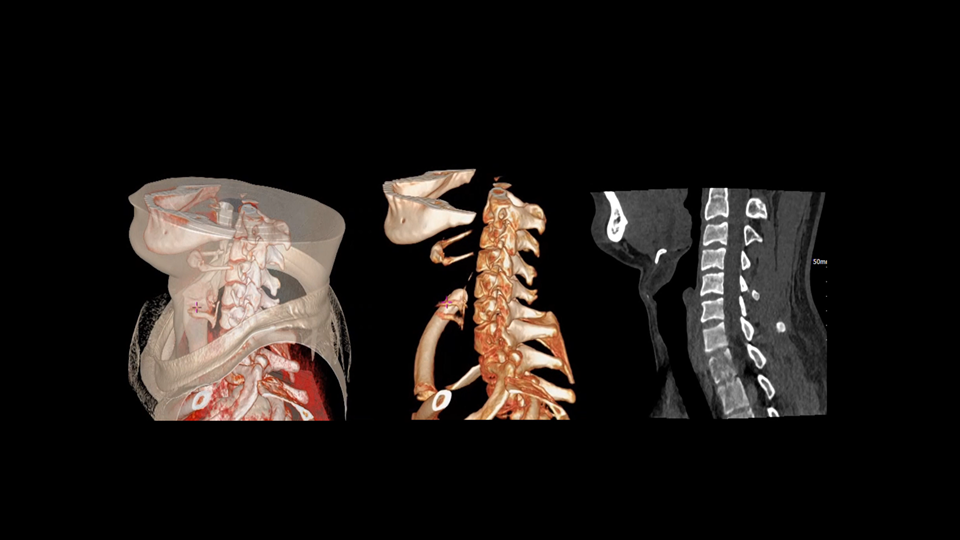

DeepMAC深度学习金属伪影校正算法

基于深度学习网络模型,应对髋关节置换体、脊柱内固定器、四肢骨科植入物、牙科修复体以及血管介入弹簧圈等各类金属植入物伪影,还原清晰解剖结构。